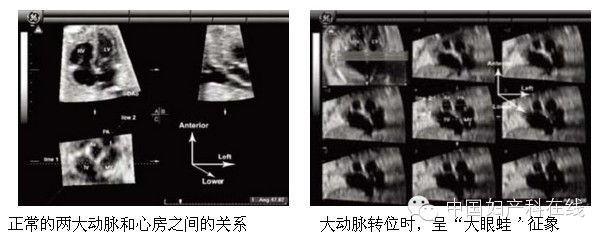

施景中教授在2008年首先描述了“大眼蛙”征象,用于诊断大动脉转位的特征性改变,采用该技术诊断大动脉转位,可以克服胎儿体位不理想的限制,同时降低对扫描手法的要求,使得大动脉转位的诊断变得非常容易。获得STIC数据后,测量心底大血管短轴平面二三尖瓣环连线和主肺动脉连线之间的夹角,正常时该夹角呈锐角(左下图);大动脉转位时,两条连线呈平行状态(右下图),主动脉、肺动脉呈左右排列,与左右房一起构成如“大眼蛙”形态图像。